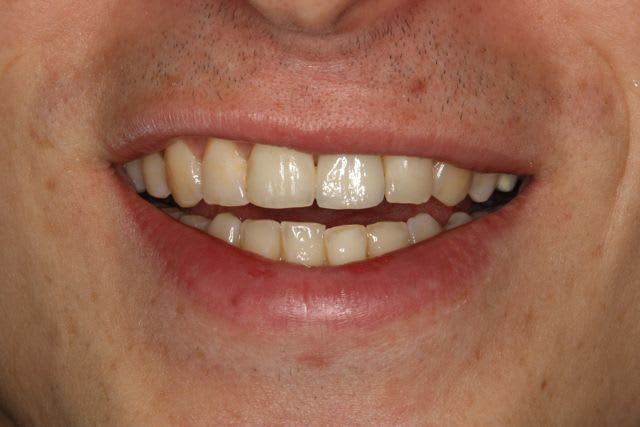

Par contre une petite remarque pourquoi avoir fait une couronne aussi triangulaire? Accentuer le coté rectangulaire aurait permis une formation et un maintien plus facile de la papille distale. De plus cela aurait plus symétrique. Donc plus esthétique.

+1 pour la remarque sur la forme de la couronne

pour la forme de la couronne c'est vrai, je suis 100% d'accord.

Mais comme le patient ne découvre pas, c'est pas trop important pour lui.

Malgré la 'finition au labo' le glaçage est trop marqué, ce qui rend la dent un peu trop brillante par rapport au autre d'ou l'aspect chouilla trop neuf. mais a part nous avec nos yeux trop exigent qui le voit ?